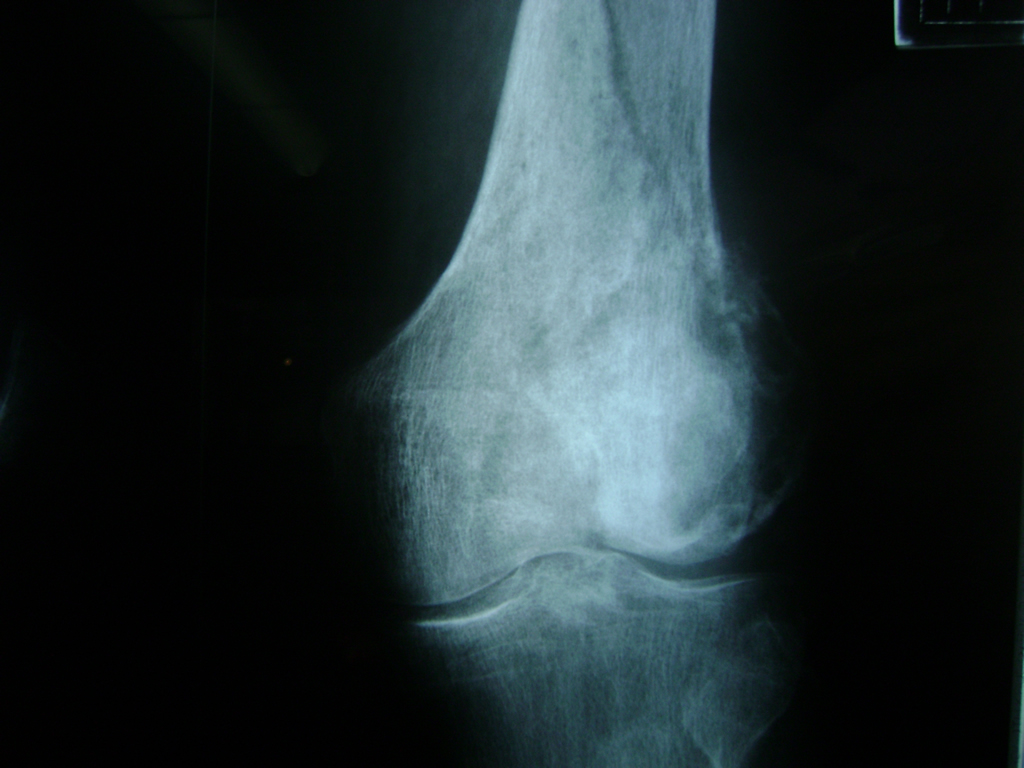

Cirugía de Rodillas